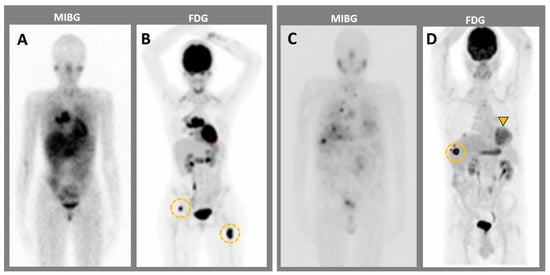

4.1. Metaiodobenzylguanidine: About the Historical Tracer

4.2. Contributions of Computed Tomography Using Dopamine and Glucose Analogues

4.4. Current Guidelines for Molecular Imaging in Diagnosis and Staging of PPGLs